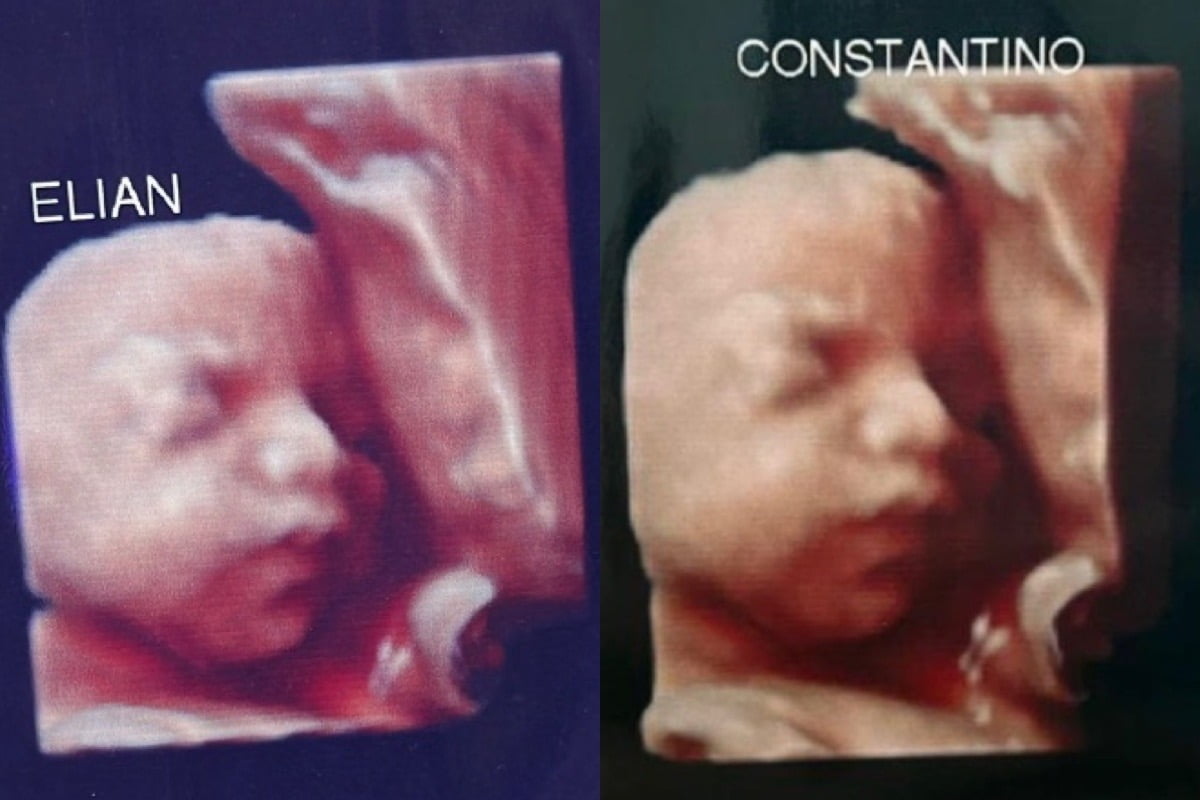

La difusión en redes sociales revela que al menos cinco madres han recibido la misma fotografía de un bebé.

La sorprendente historia comenzó cuando Antonella acudió a dicha clínica para hacerse un chequeo durante su embarazo. Sin embargo, poco después se percató de que no era la única mujer que tenía la misma imagen de un bebé en sus ecografías.

En su cuenta de Twitter, Antonella expresó su indignación y reveló que ya eran tres madres estafadas por esta clínica. Además, criticó el alto costo de los servicios que ofrecía el lugar, enfatizando en la decepción que suponía para las mujeres que esperaban ver a sus propios bebés y obtener un bonito recuerdo.

“Por ahora somos 3 mamás a las que una clínica ESTAFÓ con una foto de un bebé que no es el nuestro”, aseguró la mujer en su cuenta de Twitter.

La denuncia de Antonella pronto generó respuestas de otras mujeres que afirmaron haber pasado por la misma situación. Conforme avanzaba la discusión en la publicación, Antonella informó que el número de madres afectadas seguía aumentando.

“Está de más decir que encima que cobran carísimo uno se va ilusionado por ver a su bebé y tener un lindo recuerdo. Estamos en busca de más mamás con el mismo bebé”, añadió la mujer haciendo un llamado para encontrar a más madres que tengan el mismo bebé.

En resumen, la denuncia de Antonella sobre el uso de la misma fotografía de un bebé en las ecografías de varias madres ha generado indignación y debate en las redes sociales, mientras continúan buscando a más mujeres que hayan sufrido esta estafa para ampliar la denuncia.